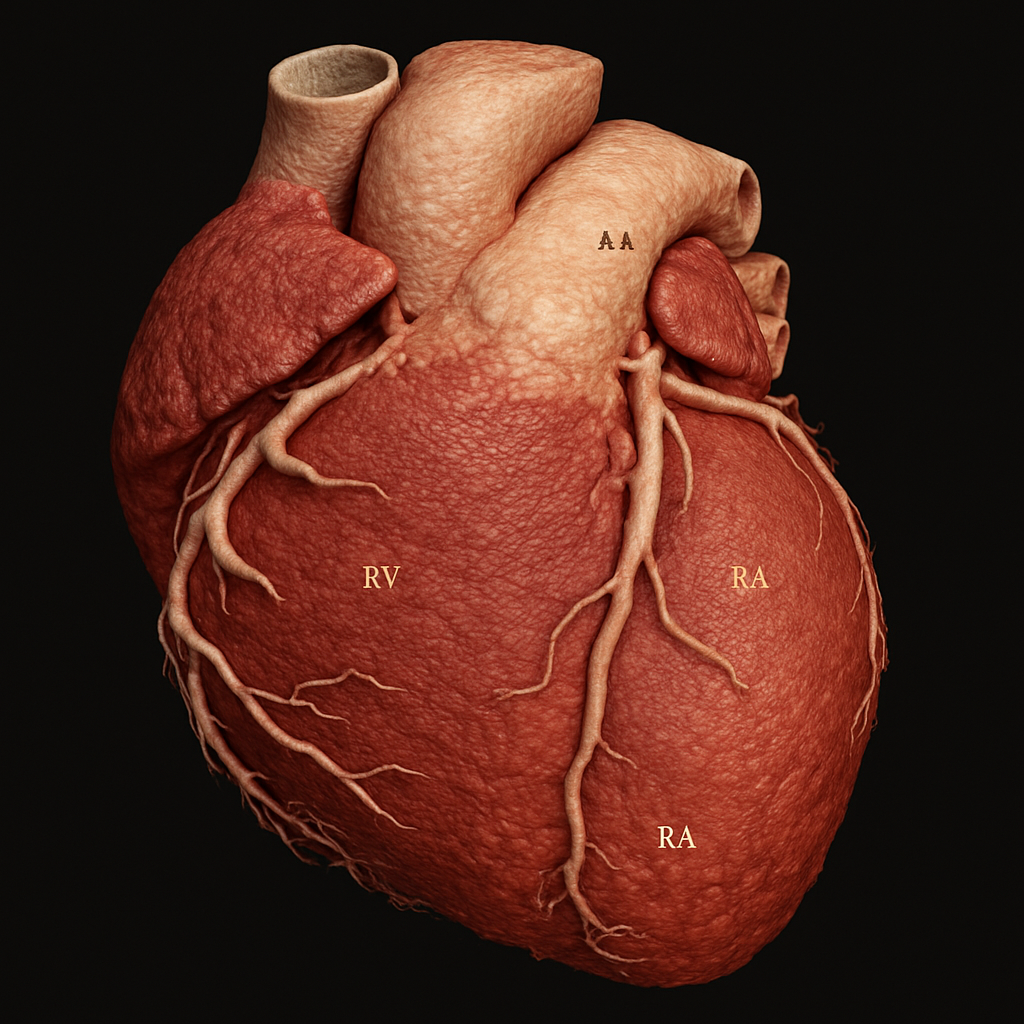

Cardiac phantom with myocardium, chambers, valves, and coronary arteries

AI-generated comprehensive cardiac phantom with all four chambers, valves, coronary arteries, great vessels,...